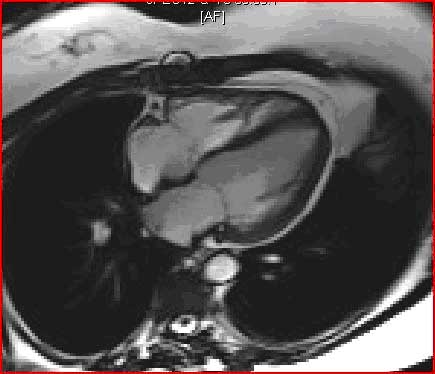

Normal Cardiac MRI